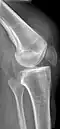

| An x-ray demonstrating quadriceps tendon rupture. Note the abnormal angle of the patella and soft-tissue swelling marked by the arrow. | |